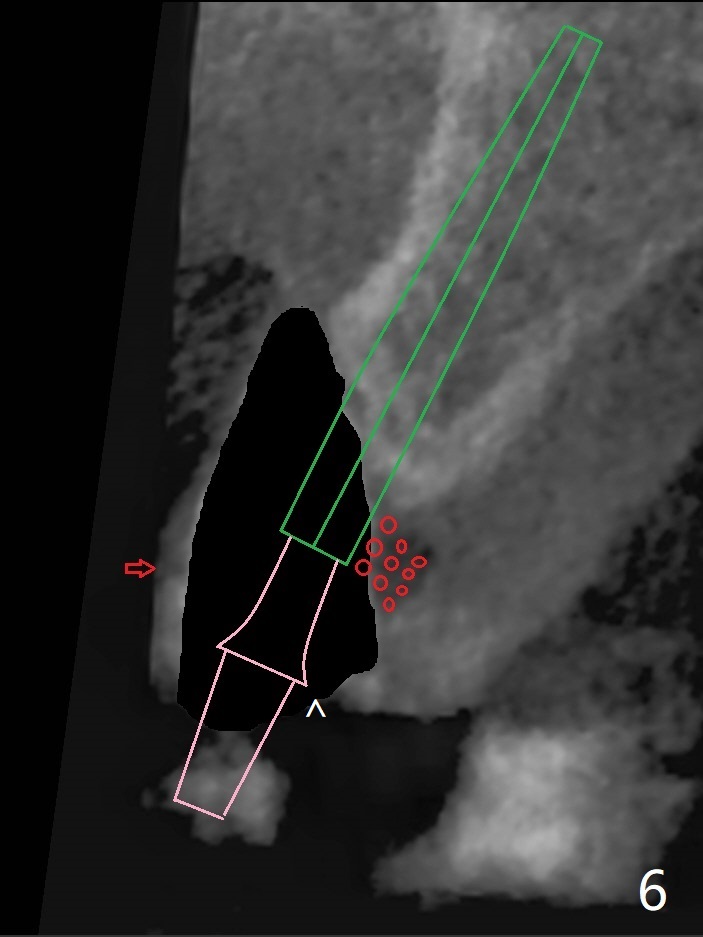

左上尖牙拔除前发现远中腭侧瘘道,拔除后发现相对牙槽嵴骨缺损(图一(术前CT):*),其实患牙根尖在颊侧骨板颊侧(图二:>),拔除后,根尖骨板缺损(图三:>),由于后者离颊侧牙槽嵴(图四:红箭头)远,骨粉修复重要性不如腭侧牙槽嵴(图四:白箭头),当窄植体植入后(图四:绿色),首先在腭侧植骨(图五:红圆圈),因为基台放置后(图六:粉红色),腭侧植骨开口狭窄(图六:白箭头)。即刻种植总是腭侧,颊侧间隙大,颊侧根尖缺损填骨应该容易(图七:橘黄色圆圈),即使不全(*),无关大局。徒手初步钻洞(图八),种植(图九)方向尚可,植骨好像完全(图十:*)。术后一周临时牙冠(11,尖牙)比侧切牙还短(图十一),随着愈合,尖牙牙冠会比双尖牙还短,因为植体偏腭侧,可能需要调整临时牙冠边缘。颊侧牙龈单纯疱疹感染,颊侧根尖仍有疼痛,腭侧瘘道缩小。